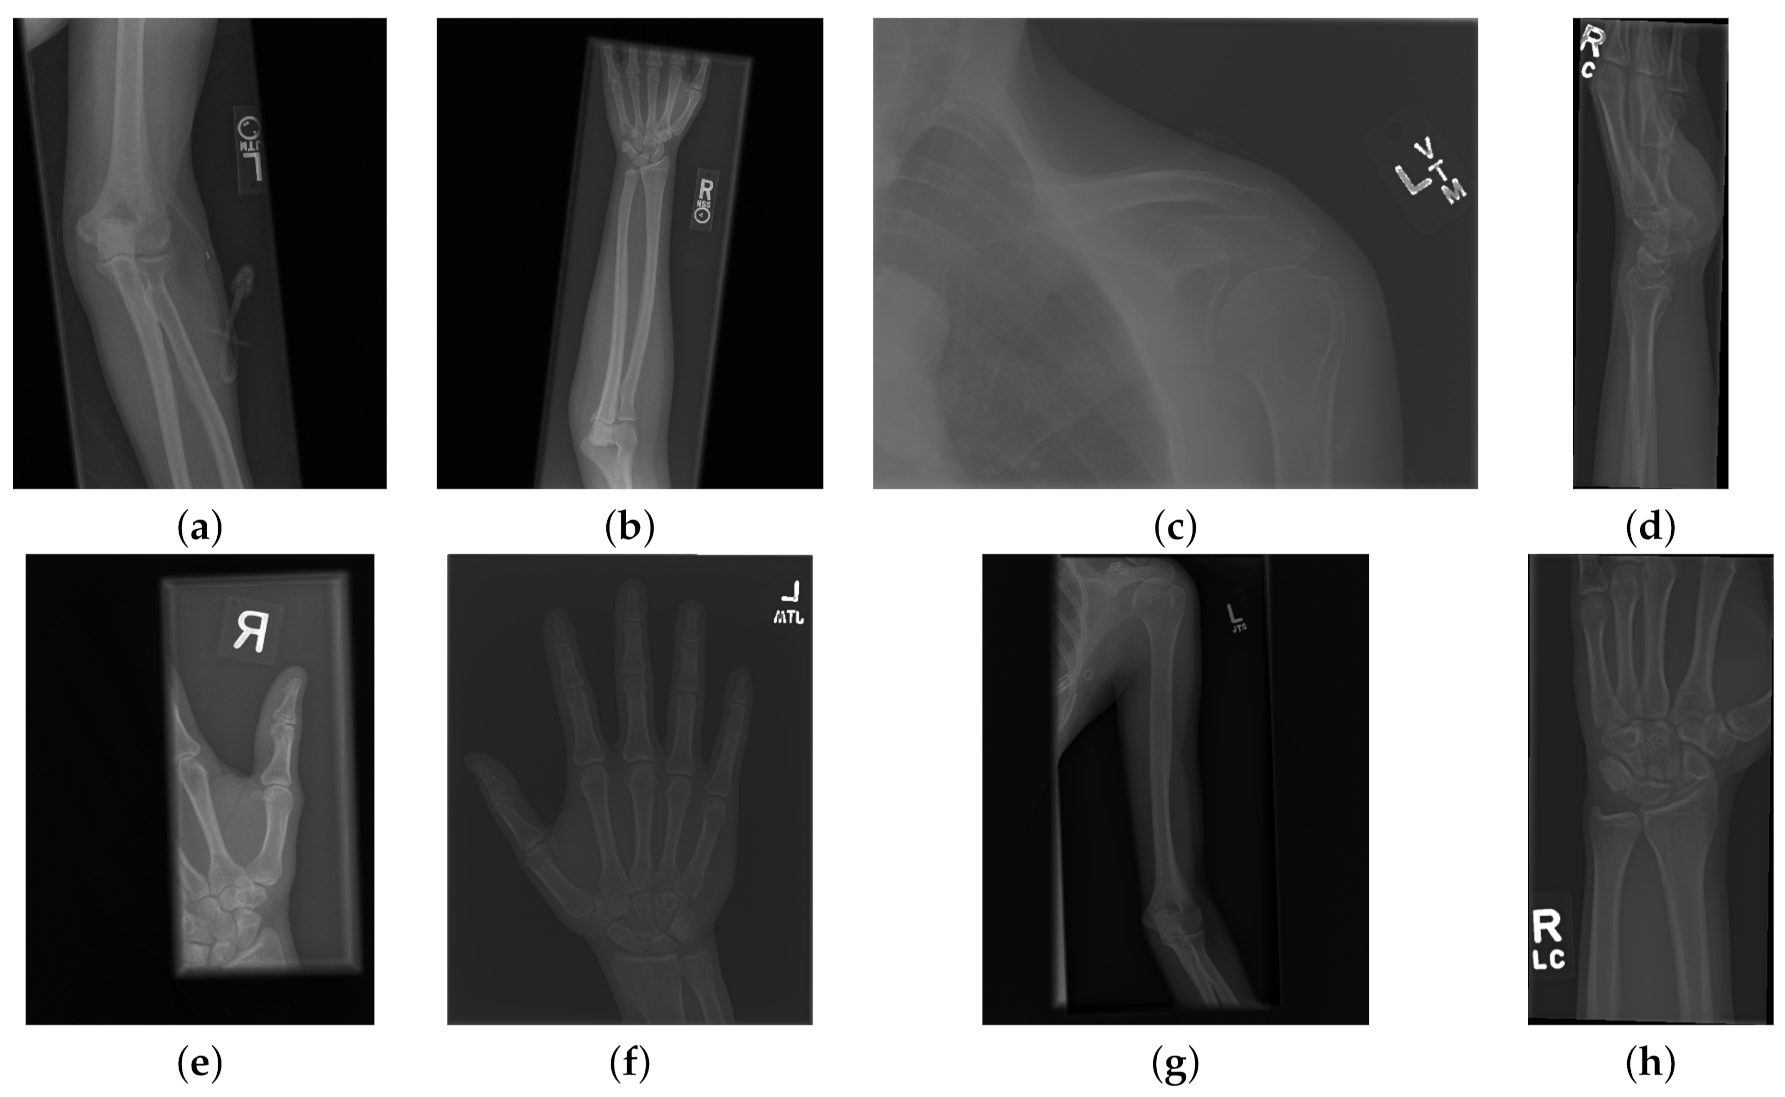

The data used to compare the 11 CNNs was obtained from the public dataset MUsculoskeletal RAdiographs (MURA) from a competition organised by researchers from Stanford University [59]. The dataset has been manually labelled by board-certified radiologists between 2001 and 2012. The studies (n = 14,656) are divided into training (n = 13,457), and validation (n = 1199). Furthermore, the studies have been allocated in groups called abnormal (i.e., those radiographs that contained fractured bones, foreign bodies such as implants, wires or screws, etc.) () or normal (). Representative normal cases are illustrated in Figure 1 and abnormal cases in Figure 2. The distribution per anatomical region is shown in Table 1. In this paper, the subset of the wrists was selected. The cases of normal and abnormal wrist radiographs is presented in Table 2. Notice that these were subdivided into four studies.

Figure 1.

Eight examples of radiographs without abnormalities (considered negative) of the Musculoskeletal Radiographs (MURA) dataset [59]. (a) Elbow, (b) Forearm, (c) Shoulder, (d) Wrist (lateral view), (d) Lateral view of Wrist, (e) Finger, (f) Hand, (g) Humerus, (h) Wrist. It should be noted the variability of the images in terms of dimensions, quality, contrast and the large number of labels (i.e., R for right and L for left), which appear in various locations.